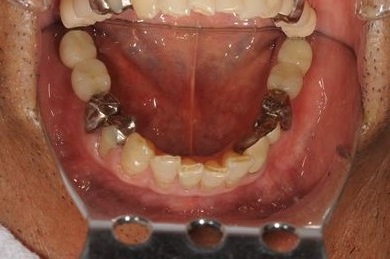

| 性別/年齢 | 男性 / 61歳 | ||||||||||||||||||||||||||||||||

| 主訴 | 奥歯のインプラント治療を希望。 | ||||||||||||||||||||||||||||||||

| 治療方針 | インプラント治療にて、機能的・審美的回復を行う。 | ||||||||||||||||||||||||||||||||

| 治療内容 | インプラント4本、メタルボンドセラミッククラウン4本 | ||||||||||||||||||||||||||||||||

| 総治療費 | 1,508,220円 | ||||||||||||||||||||||||||||||||

| 治療期間 | 7ヶ月 |